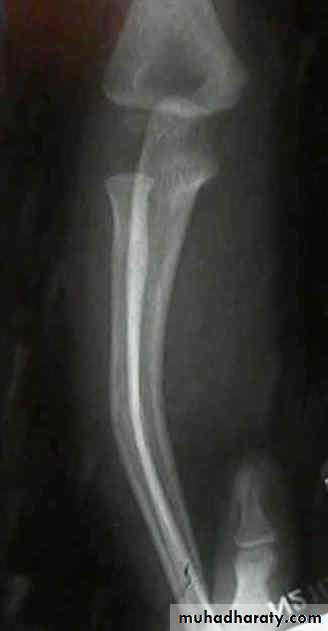

15Special types in children

Green-stick # : one cortex fractured & the opposite is compressed

Buckle fracure

Plastic deformation